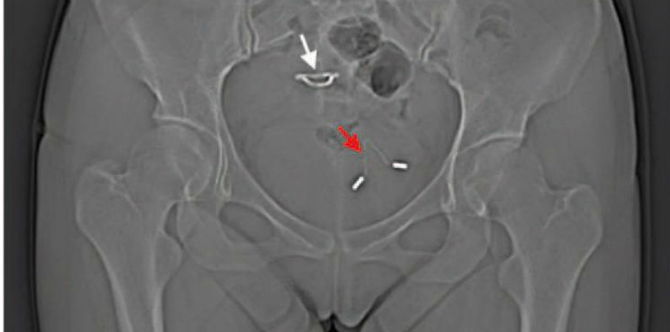

Setelah mendapat laporan ada masalah dengan kandung kemihnya, dokter di rumah sakit Jilin University melakukan pemeriksaan rontgen pada panggul ibu yang tidak disebutkan namanya tersebut. Hal mengejutkan pun terjadi, KB IUD yang dulu dinyatakan hilang terlihat dalam hasil rontgen.

Dari hasil pemeriksaan sinar X, terlihat bahwa ada dua KB IUD yang tertanam di dalam tubuh pasien tersebut. Satu yang baru saja dimasukkan setelah operasi cesar, dan satu lagi KB IUD berpindah tempat ke dalam kandung kemihnya.